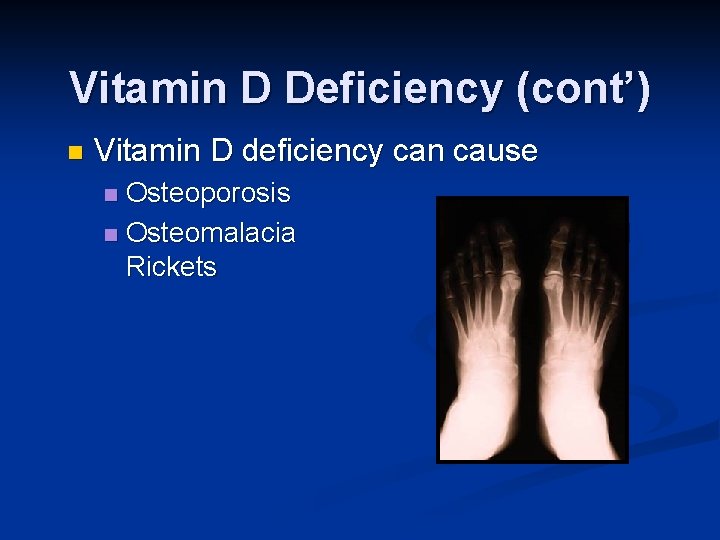

Vitamin D Deficiency (cont’) n Vitamin D deficiency can cause Osteoporosis n Osteomalacia and Rickets n